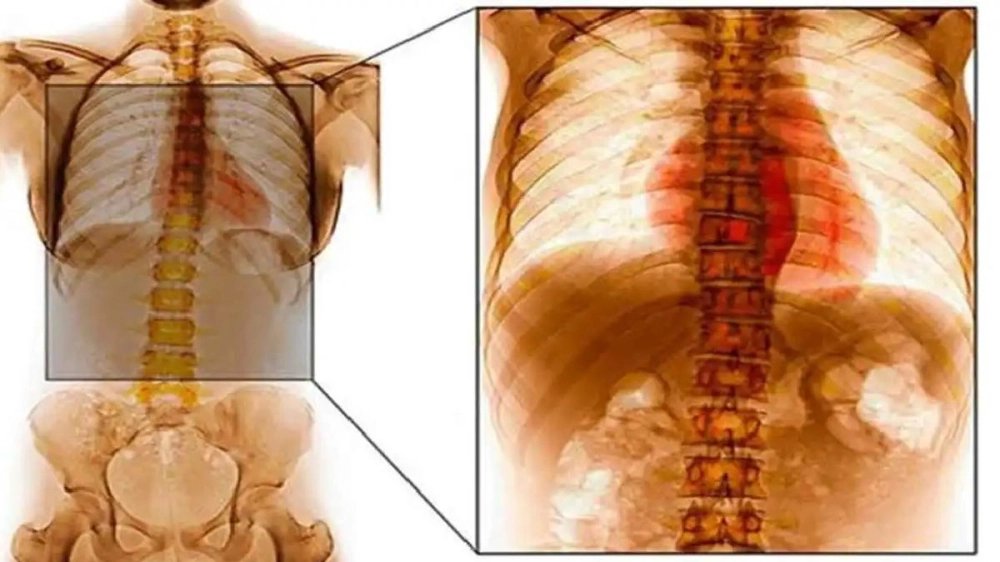

আজকাল ওয়েবডেস্ক: বিশ্বজুড়ে যক্ষ্মা বা টিউবারকুলোসিস (টিবি) এখনও এক আতঙ্কের নাম। ফুসফুসে এর প্রকোপ সর্বাধিক হলেও, শরীরের অন্য অঙ্গও কিন্তু এই জীবাণুর হানাদারি থেকে পুরোপুরি মুক্ত নয়। রক্তপ্রবাহের মাধ্যমে এই জীবাণু যখন হাড়ে, বিশেষ করে শিরদাঁড়া বা মেরুদণ্ডে পৌঁছয়, তখন পরিস্থিতি অত্যন্ত জটিল হয়ে উঠতে পারে। চিকিৎসাবিজ্ঞানের ভাষায় একেই বলা হয় স্পাইনাল টিউবারকুলোসিস বা ‘পট’স ডিজিজ’। সময়মতো রোগ নির্ণয় এবং চিকিৎসার অভাবে যা ডেকে আনতে পারে স্থায়ী পঙ্গুত্ব।

স্পাইনাল টিবি-র জন্য দায়ী জীবাণুটি হল ‘মাইকোব্যাকটেরিয়াম টিউবারকুলোসিস’, যা ফুসফুসের টিবি-র জন্যও দায়ী। মূলত, ফুসফুসে প্রাথমিক সংক্রমণের পরেই এই জীবাণু রক্তের মাধ্যমে শরীরের অন্যত্র ছড়িয়ে পড়ে। মেরুদণ্ড হল এর অন্যতম পছন্দের আশ্রয়স্থল। বিশেষত, পিঠের নীচের অংশ বা থোরাসিক স্পাইন এতে বেশি আক্রান্ত হয়।

স্পাইনাল টিবি নিয়ে আতঙ্কিত হওয়ার কারণ নেই। সঠিক সময়ে রোগ নির্ণয় করা গেলে এবং সম্পূর্ণ চিকিৎসা করালে এই রোগ সম্পূর্ণ নিরাময়যোগ্য। এক্স-রে, সিটি স্ক্যান এবং এমআরআই-এর মতো পরীক্ষার মাধ্যমে মেরুদণ্ডের পরিস্থিতি সম্পর্কে নিশ্চিত হওয়া যায়। অনেক সময় বায়োপসি বা ফ্লুইড পরীক্ষা করে জীবাণুর উপস্থিতি সম্পর্কেও নিশ্চিত হন চিকিৎসকেরা।